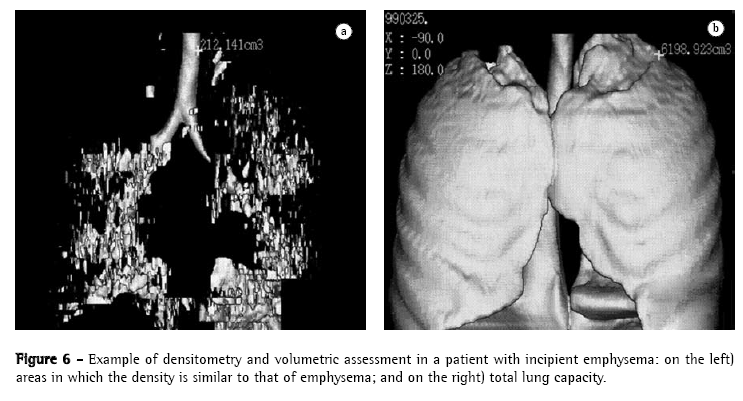

The acquisition of data volume in a single breath-hold allows us to reconstruct data in three-dimensional format, using three-dimensional CT. This technological resource has been more frequently used in the investigation of chest alterations.(51-56) One of the pioneers in the dissemination of the technique(56) demonstrated its efficiency in the quantification of emphysema. The denomination three-dimensional CT-guided densitometry and volumetric assessment for emphysema(55) has been currently suggested for this quantification process of the volume of emphysema, based on data obtained through spiral CT scan with three-dimensional representation of emphysematous lesions (Figures 5 and 6). The test measures the whole pulmonary volume with abnormal density and, also, the whole lung volume with normal density,(41,56-61) setting them apart based on the separation threshold generally selected at −950 HU, as per the suggestion of one author. Among the practical applications of the technique, one study demonstrated that normal CT-guided pulmonary densitometry and volumetric assessment excels HRCT, and should be included in the preoperative evaluation of patients for whom surgery for volumetric reduction of the lungs has been indicated.(58) This clinical applicability of three-dimensional CT-guided densitometry and volumetric assessment used for the same purpose has been known in Brazil for some time.(39) In a recent consensus, the use of three-dimensional CT-guided densitometry and volumetric assessment was suggested for the evaluation of therapeutic efficacy in the treatment of emphysema, replacing FEV.(59)

With the establishment of normality reference values,(55) it is already possible, as well, to use three-dimensional CT-guided densitometry and volumetric assessment in the early diagnosis and graduation of the severity of the disease, and this early detection and demonstration of three-dimensional imaging to the patient has been suggested as potentially useful in techniques of smoking cessation.(60) In addition, it also seems promising in the evaluation of patients whose occupational activities can induce the development of emphysema.